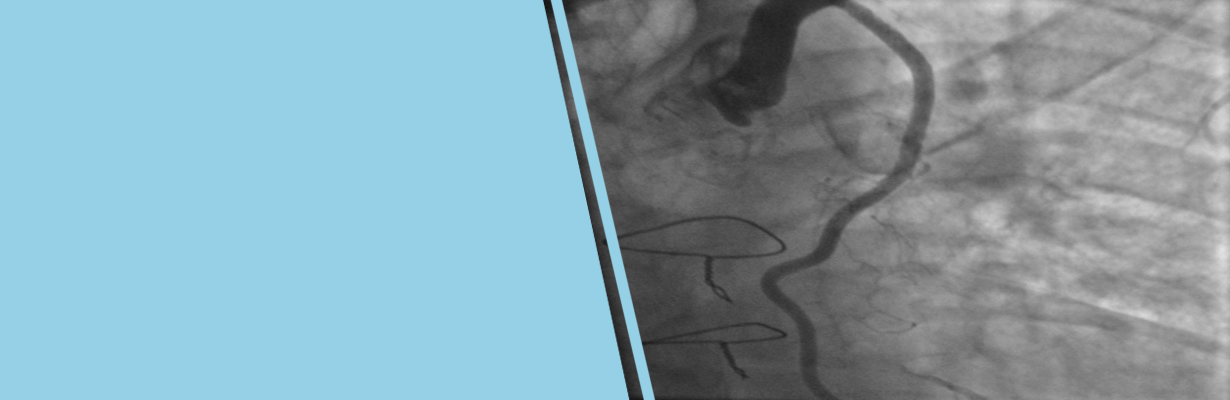

In this video, Dr. OP. Yadava, Chief Executive Officer & Chief Cardiac Surgeon, National Heart Institute, New Delhi, tells when the bypass surgery is done along with angiography. This type of surgery is known as hybrid cardiac surgery.